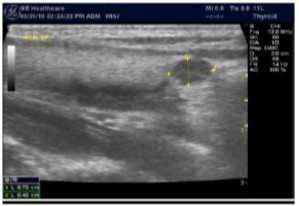

Parathyroid Glands Pathology:

In our study many patients were found to have nodules look very much like PT adenoma, Figure 7 below. At least, 4 patients were subsequently confirmed to have parathyroid adenomas, Figure 8 and 2 patients underwent surgery

Despite the fact that nodular pathology was found to be very prevalent among our study population, it has been found difficult to differentiate between thyroid and parathyroid pathology using ultrasound alone. However, some characteristics of the parathyroid glands might suggest parathyroid pathology in the context of the clinical picture of secondary or tertiary hyperparathyroidism which is very prevalent in ESKD patients’ populations.

Figure 7.Thyroid nodule suspicious for Parathyroid adenoma due to its location

Thyroid nodule suspicious for Parathyroid adenoma due to its location

Figure 8.Nodule that proven to be a parathyroid adenoma, volume =5265 mm3

Nodule that proven to be a parathyroid adenoma, volume =5265 mm3

There are 4 parathyroid glands (2 superior, 2 inferior) imbedded within the thyroid gland. The parathyroid glands are bean-like shape and small (20-40 mg) 25. Sonographically, the parathyroid glands have the following features 25:

Hyperplastic glands: hypoechoic, volume <500 mm3.

Nodular glands: hypoechoic. Volume >500 mm3

Histologically, if the excised gland has volume <500 mm3 it is said to be hyperplastic and if the volume is more than 500 mm3 it is nodular hyperplasia in 80% of cases26. In secondary HPT, the increase in the volume of parathyroid glands is associated with increase in vascularity, as evident in Color Doppler imaging 27.